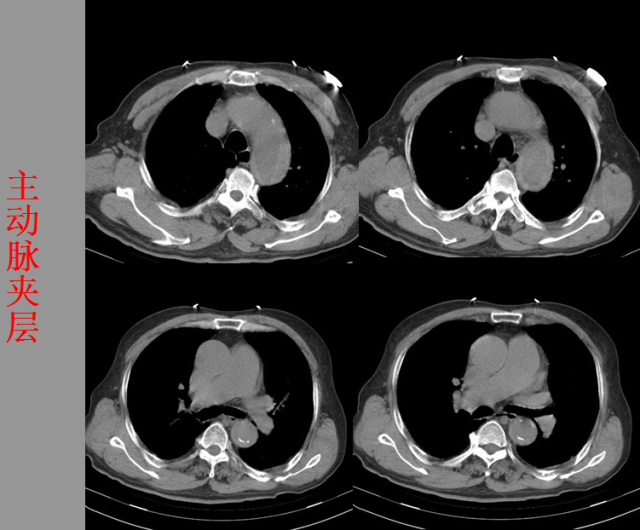

急胸症篇

04